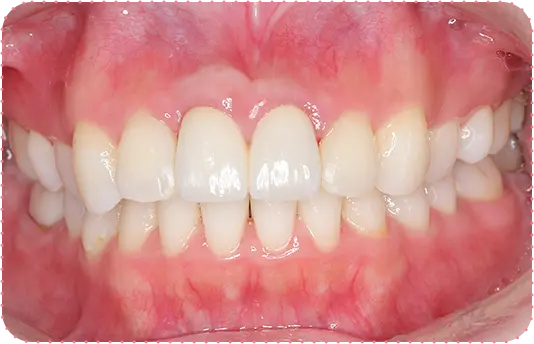

Before

After

主訴

前歯をきれいにしたい

治療期間

8か月

治療費

40万円

治療内容

右上2番をマウスピース矯正で移動してラミネートべニアにて修復

治療のリスク

【マウスピース】

矯正装置を初めて装着した時は、違和感や圧迫感、疼痛などを感じる場合があります。

歯根吸収や歯肉の退縮が起こる場合があります。

1日の装着時間が長いため、口内清掃不足だとむし歯・歯周病のリスクが高くなります。

歯の移動後に保定装置(リテーナー)の使用が不十分の際は、後戻りが生じる場合があります。

マウスピースの装着時間が少ないと治療期間が長引く場合があります。

【セラミック】

咬み合わせによっては、セラミックが欠ける可能性があります。